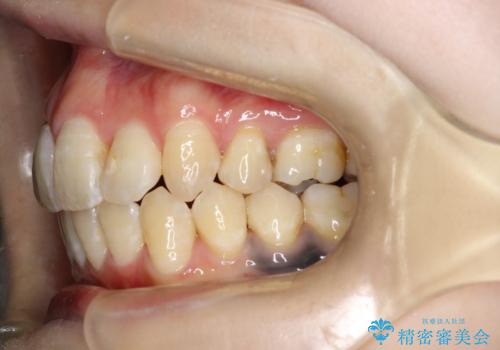

重度のガタガタ ワイヤーによる抜歯矯正

抜歯したスペースを使うことで、ガタガタと出っ歯を改善することができました。